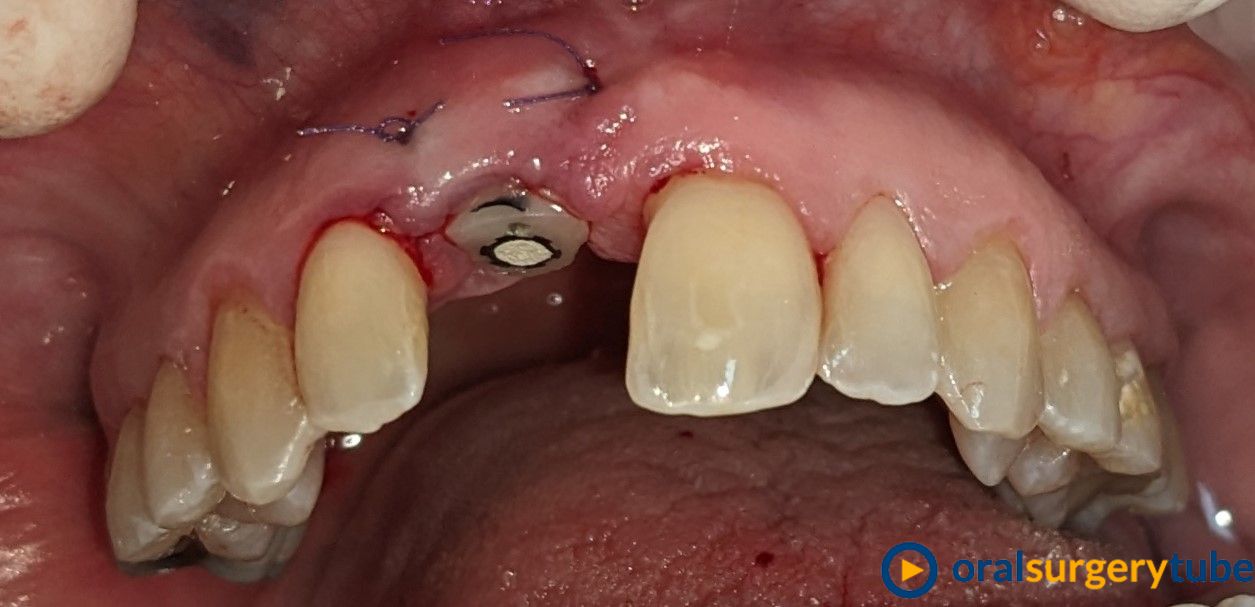

Paciente mujer joven, fumadora y de higiene regular. Con periodontitis moderada estabilizada pero con mal mantenimiento y con un proceso muy avanzado en el 21. Se le realiza en el mismo acto la extracción, legrado y lavado profuso, fresado y colocación guiada del implante con torque de 20N . Y después se regenera el aveolo con mix de autólogo de rama rascado con un micross y Bioss collagen y un injerto de tuberosidad en vestibular. No se hace carga inmediata por la baja estabilidad, se coloca y tapón de cicatrización y periacryl para sellar. Buscando un tratamiento similar (salvando mis infinitas limitaciones y distancias) a los protocolos de actuación de dos gigantes como Mesquita (implanteperio) y/o el de David González y su articulo de 3 Layers para alveolos sin tabla. Me decido por esta opción ya que todo lo que fuese levantar un colgajo sería al 100% un desastre estético y no estoy capacitado para un bloque mixto de tuberosidad ósea y blanda. Quizá haya fallado mi diagnostico o mi técnica.

Aparentemente la cicatrización es buena, asintomático y con buen aspecto. Pero en el control a 4 meses veo muchísima reabsorción de mi regeneración en vestíbulo. Sería por el potencial osteoclástico en ese lecho? o por no poner una capa de reabsorción lenta en la parte más externa?... en unos días probaré a ver si no me quedo con el implante en la mano.